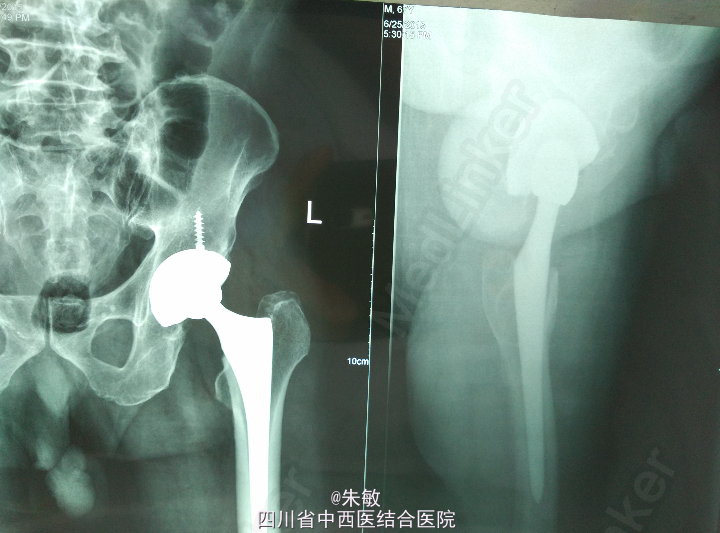

诊断及手术指征明确,已告知患方病情,其经考虑后选择手术治疗。术前检查未见绝对手术禁忌,拟订于明日在全麻下行左侧人工全髋关节置换术,术前需合血备用,术前术后需预防性应用抗生素,一旦感染,可导致手术失败、人工关节取出、化脓性关节炎等严重后果

术后2周复查

感谢分享。从片子上看患者双侧股骨头坏死合并髋关节OA诊断明确。患者为老年男性合并骨质疏松,术后注意防范假体周围骨折。

患者左侧髋关节出现关节间隙狭窄,股骨头轻度骨质塌陷,病情严重,故采用左全髋置换术。术后应注意减轻右侧负重,如出现症状可行牵引等保守治疗。